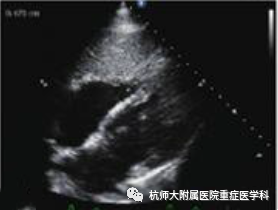

c.心尖四腔心切面:位置选择:心尖处,超声探头声束朝向患者右肩方向指向心底;操作过程中在胸骨旁长轴切面沿左心室向心尖滑动;当室间隔刚刚消失时,将超声探头旋转90°~120°;将超声探头向前倾斜,声束指向右肩,找到标准平面。

什么是超声容积探头重症心脏超声图像的获取_https://www.jmylbn.com_新闻资讯_第17张什么是超声容积探头重症心脏超声图像的获取_https://www.jmylbn.com_新闻资讯_第18张

主要评估内容:(1)各腔室大小、比例;(2)室壁的运动;(3)测量射血分数;(4)二尖瓣和三尖瓣瓣膜的形态结构及瓣口血流情况。